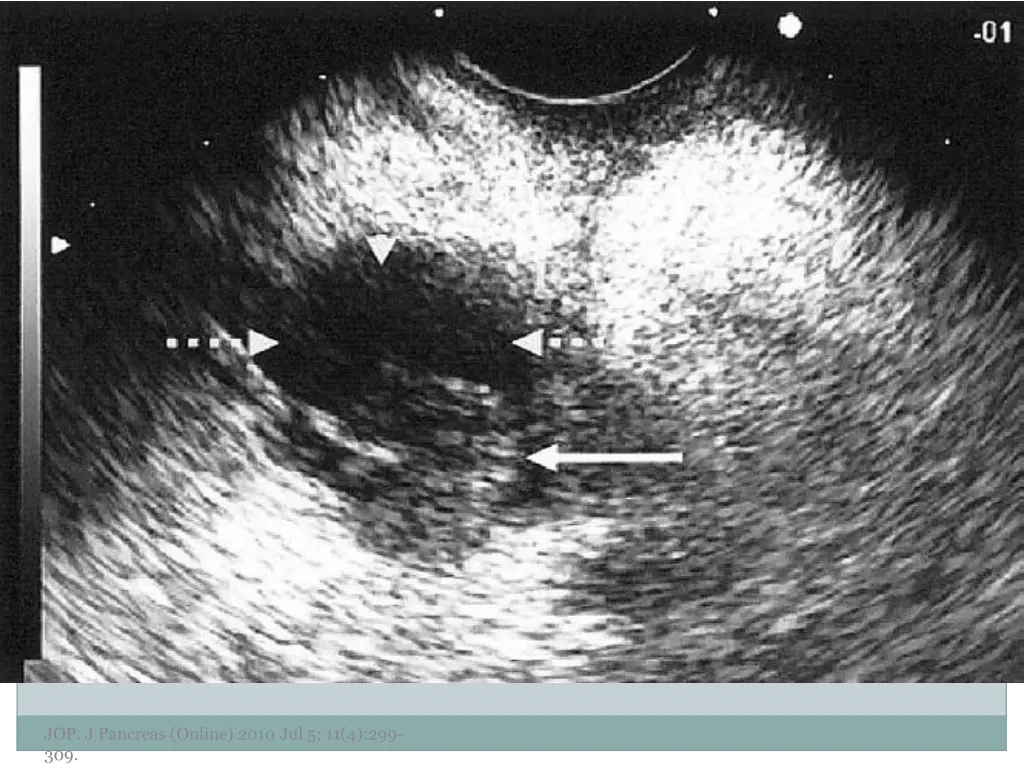

7. EUS Morphology Cyst wall Thick vs. thin Solid component Associated with malignancy Septations Micro vs. macrocystic Ductal abnormalities Main duct vs. side duct Number of cyst Lymphadenopathy EUS morphology can correctly differentiate mucinous from non-mucinous cystic lesions approximately 50% of the time JOP. J Pancreas (Online) 2010 Jul 5; 11(4):299- 309.

10. Examples of Morphology JOP. J Pancreas (Online) 2010 Jul 5; 11(4):299- 309.

11. JOP. J Pancreas (Online) 2010 Jul 5; 11(4):299- 309.

12. JOP. J Pancreas (Online) 2010 Jul 5; 11(4):299- 309.

13. JOP. J Pancreas (Online) 2010 Jul 5; 11(4):299- 309.